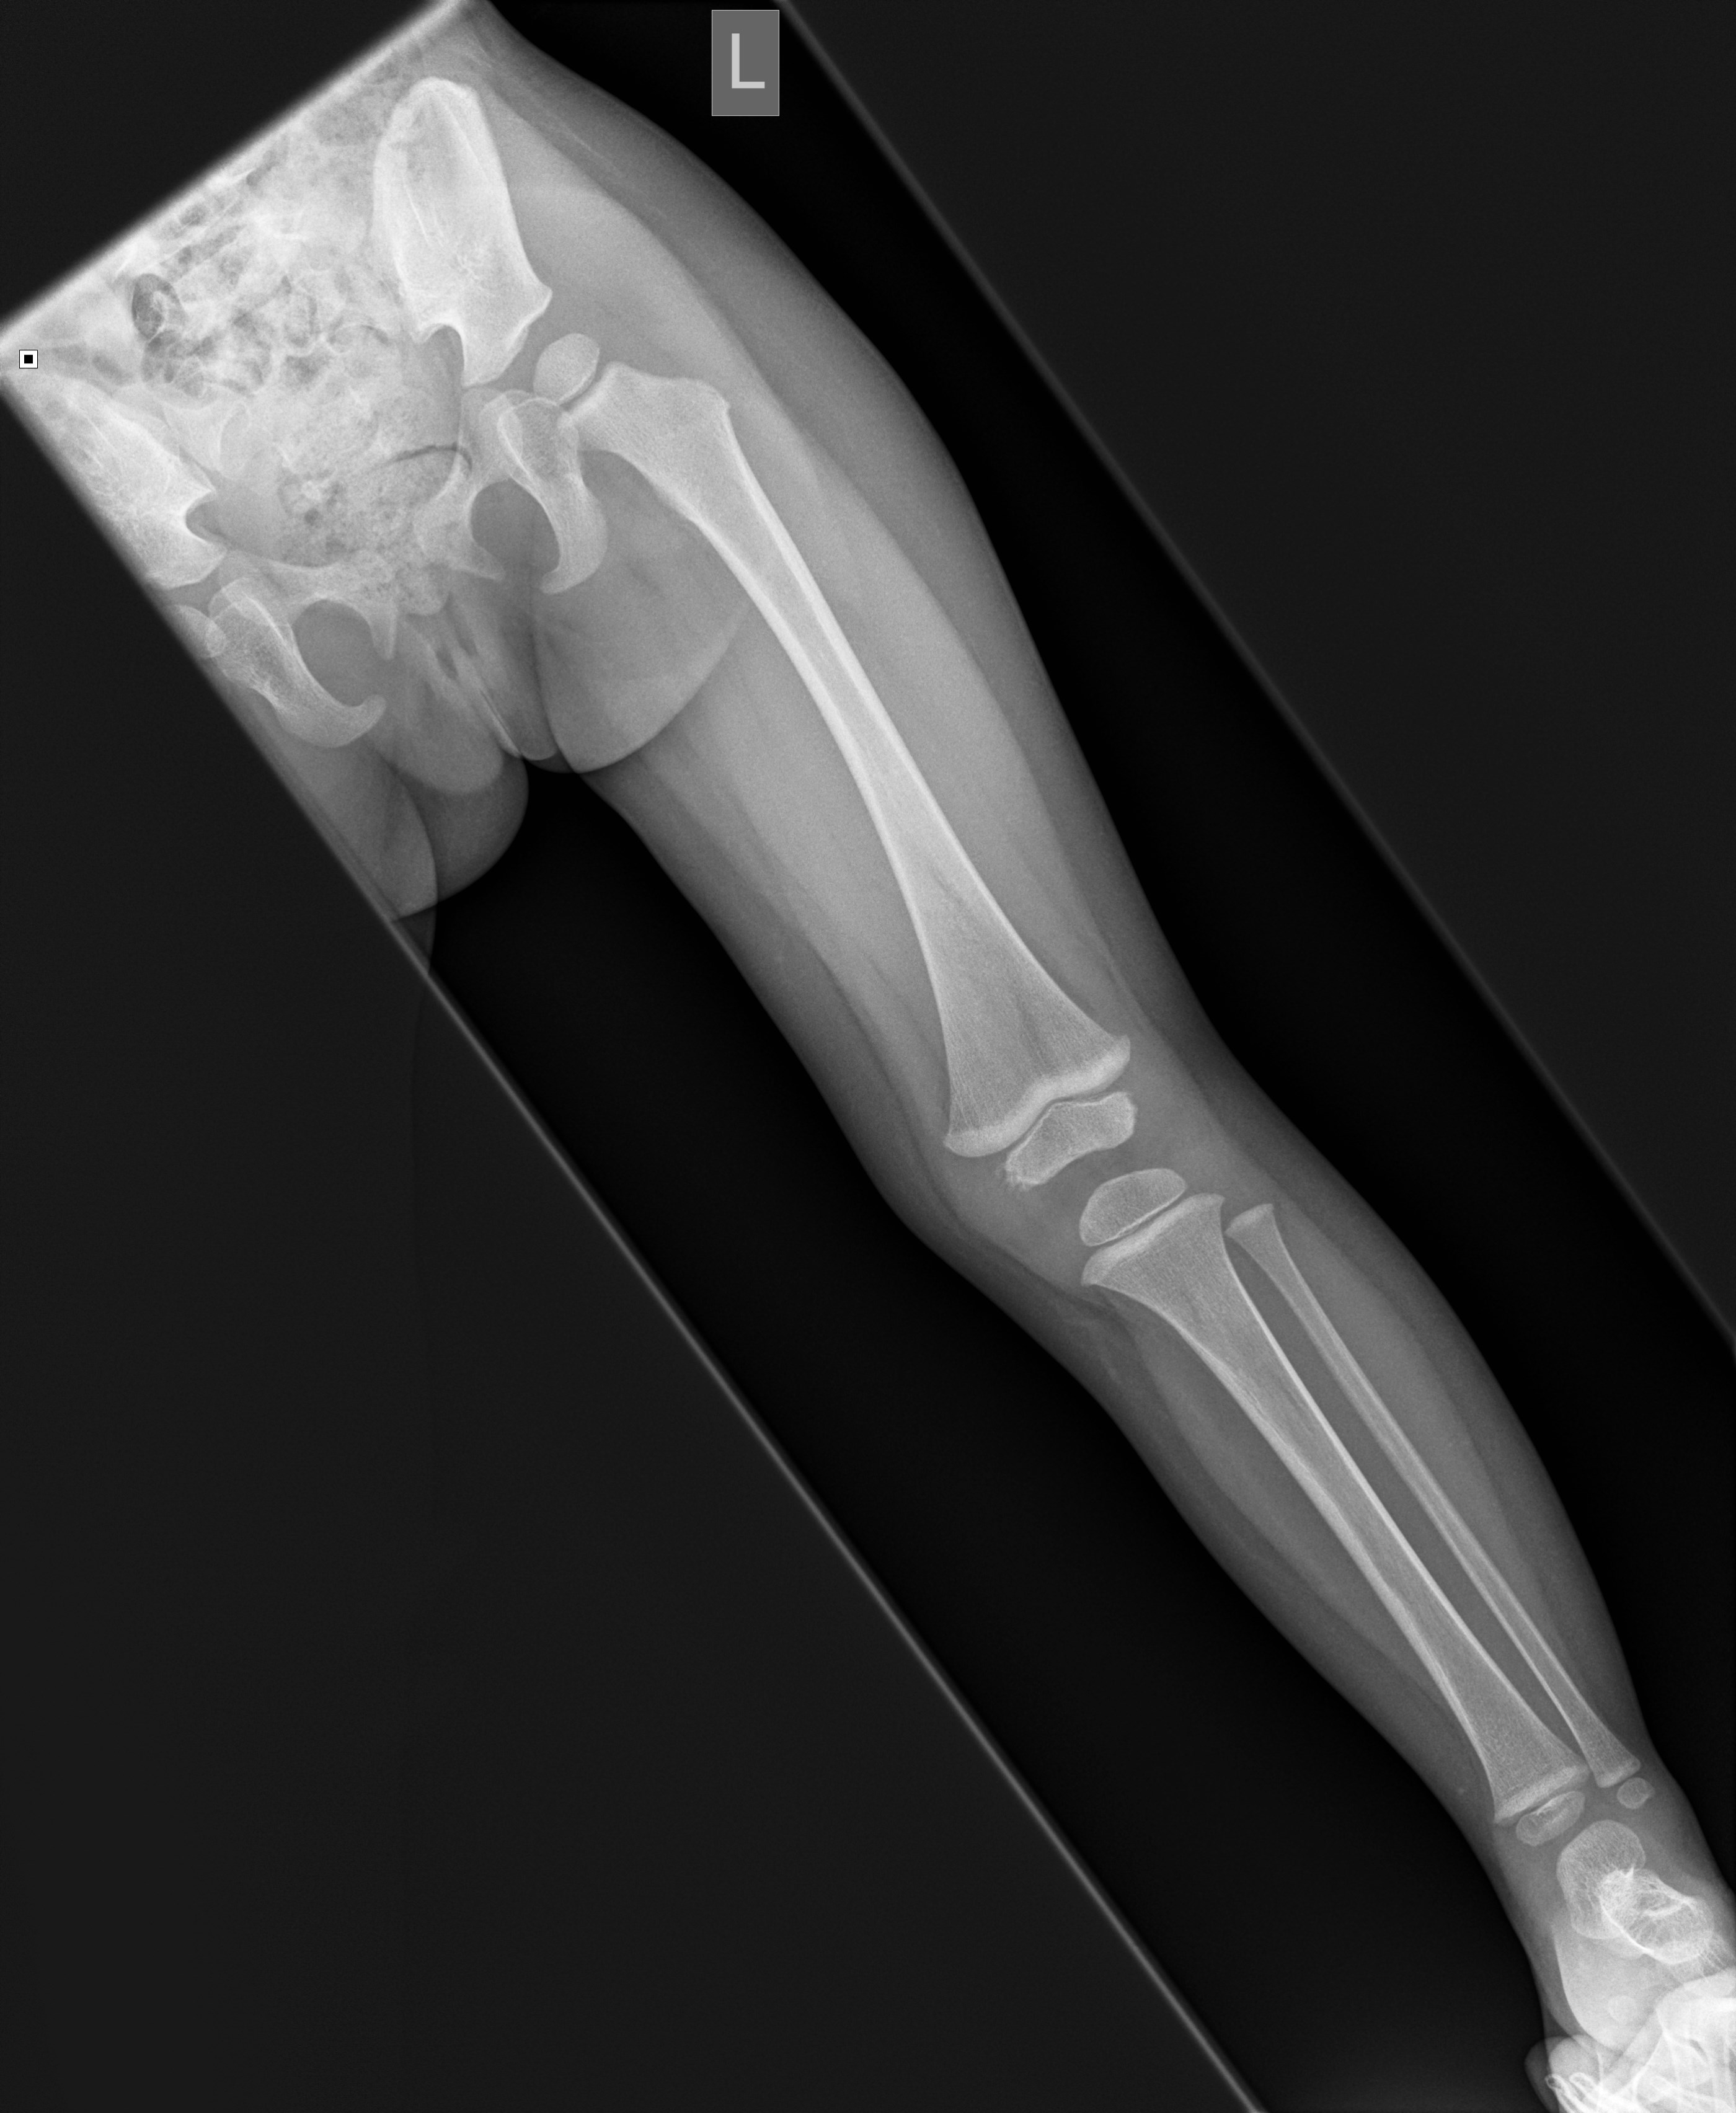

Wholeleg radiograph of the lower extremity revealed a Openi Pediatric Leg X Ray Diagnosis can be confirmed with plain radiographs of the tibia. Lower limb radiography for pediatric patients involves imaging of the pelvis, hip joint, femur, knee joint, tibia, fibula, ankle joint, and foot. Pediatric tibial shaft fractures are the third most common long bone fracture in children. This is a repository of normal pediatric bone xrays and their examples for a. Pediatric Leg X Ray.

OrthoKids Leg Length Discrepancy Pediatric Leg X Ray Pediatric tibial shaft fractures are the third most common long bone fracture in children. Leg and foot problems in childhood are common causes of parental concern. Learn what your child might experience, how to prepare, benefits, risks and much more. This article lists examples of normal imaging of the pediatric patients divided by region, modality, and age. Lower limb radiography. Pediatric Leg X Ray.